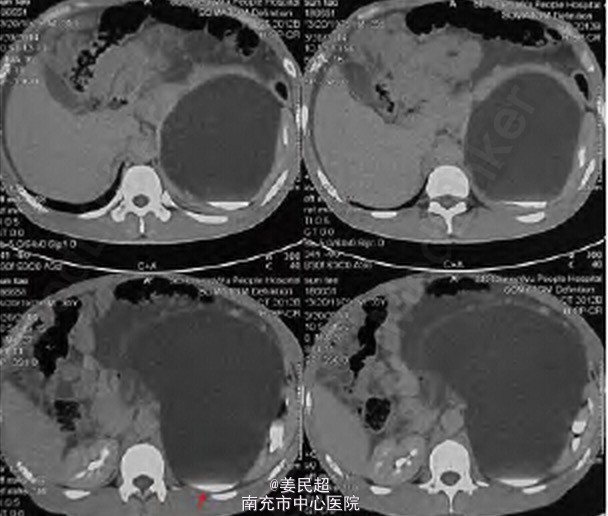

患者,男,34 岁,因“发现腹腔内巨大囊性占位4 天”入院。

腹膨隆,腹部可触及一巨大囊性占位,无压痛及反跳痛,双肾区无叩痛,左肾区叩击伴明显液波震颤感。 CT 可见: 腹腔内见巨大囊性低密度灶,边界清,最大截面约22cm ×15cm,与左肾关系密切,左肾明显受压,注入造影剂后排泄期可见病灶内少量造影剂进入。于膀胱后方可见水样密度管状结构。 逆行肾盂造影检查未见异常输尿管口,造影检查提示左侧受压肾脏肾盂显影,形态失常,右侧未见明显异常